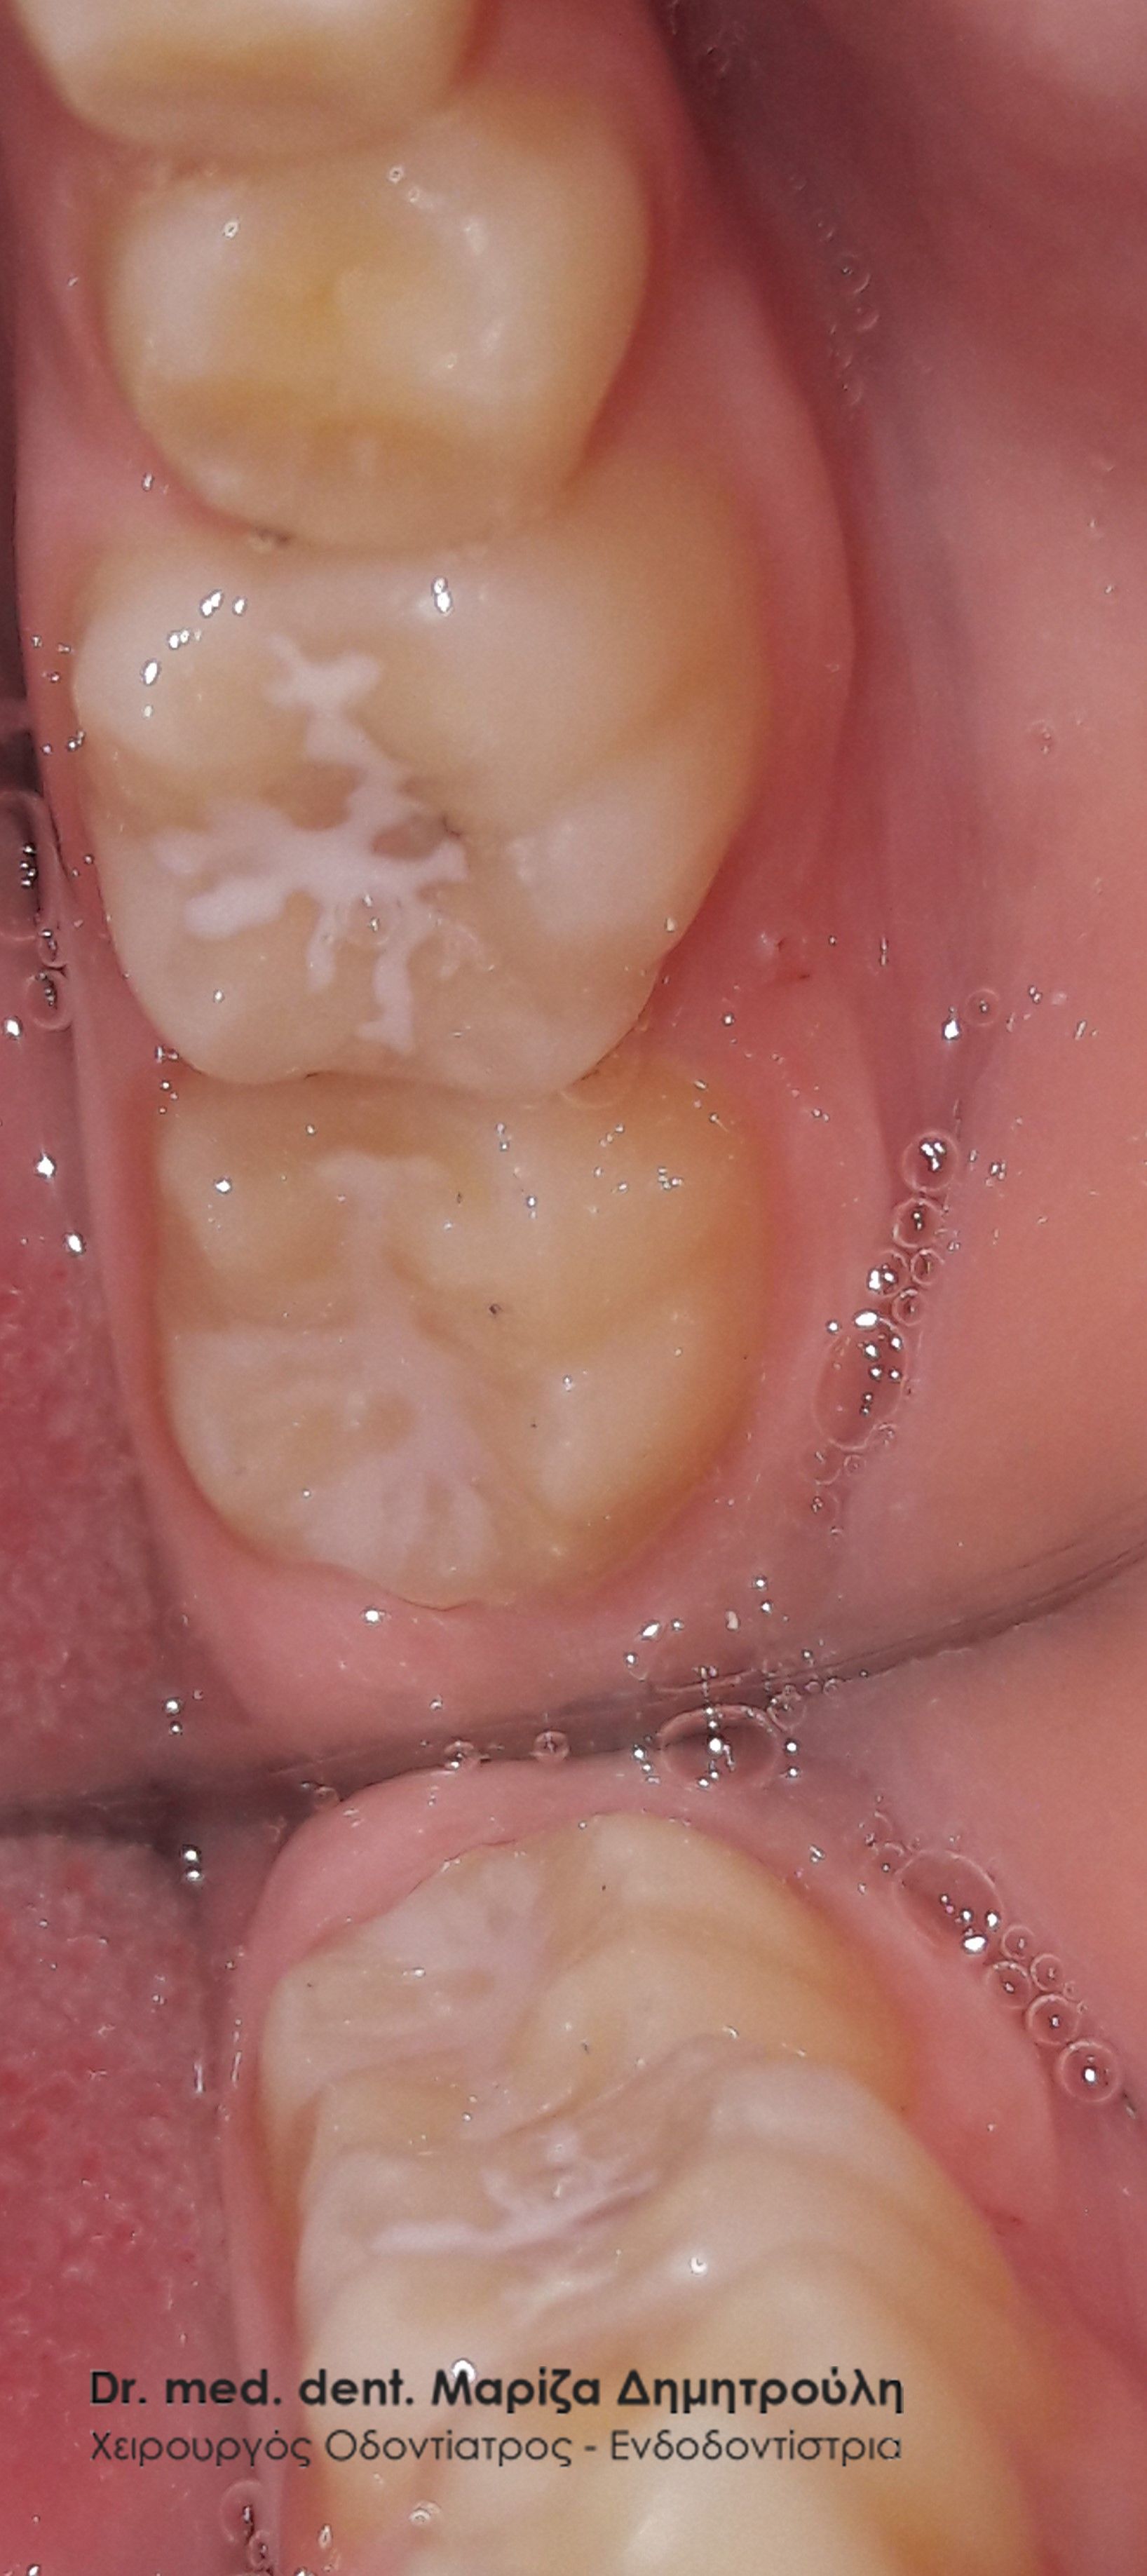

Περιστατικό – Sealant / προληπτική κάλυψη οπών και σχισμών

Στο αγόρι αυτό τοποθετήθηκε προληπτική κάλυψη στη μασητική επιφάνεια του μόνιμου κάτω πρώτου γομφίου, ώστε το δόντι να είναι προστατευμένο από την τερηδόνα. Η κάλυψη της μασητικής επιφάνειας ενός δοντιού με sealant μειώνει την κατακράτηση υπολειμμάτων τροφών στις σχισμές και τις αύλακες του δοντιού αυτού με αποτέλεσμα να συγκεντρώνονται και λιγότερα μικρόβια στο δόντι. Παράλληλα το παιδί μπορεί να βουρτσίζει πιο αποτελεσματικά και εύκολα τα πίσω δόντια καθώς μειώνονται οι πτυχές του δοντιού, όπου παγιδεύονται συνήθως τροφές.

Ο χρόνος ζωής ενός sealant κυμαίνεται από 2 – 5 χρόνια.

ΜΕΤΑ